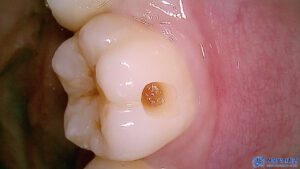

마무리 후 사진입니다.

환자분께서는 충치 정도에 따라

정직하게 진단해주는 모습이 좋았고,

치료도 너무 잘 받아보셨다고 하셨습니다.

신경치료 진행하면서

많이 편해지셨다고 하셨고,

크라운 색상도 다른치아들과 자연스럽고

씌운것도 괜찮으시다고

만족해주셨습니다.